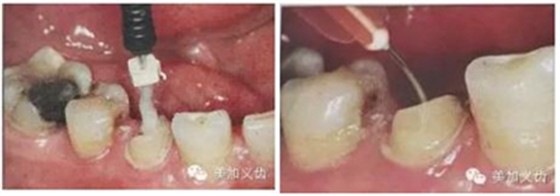

(超聲預(yù)備根管完成)(插入橢圓形纖維樁)

ELLIPSON 技術(shù),采用超聲預(yù)備鉆對扁圓形根管進(jìn)行直接預(yù)備,改善了樁核根管的適應(yīng)性。有效的保存了根管牙體組織,從而增強(qiáng)了粘接面積,,減少樹脂水門汀的厚度,提高根管內(nèi)纖維樁的粘接強(qiáng)度。